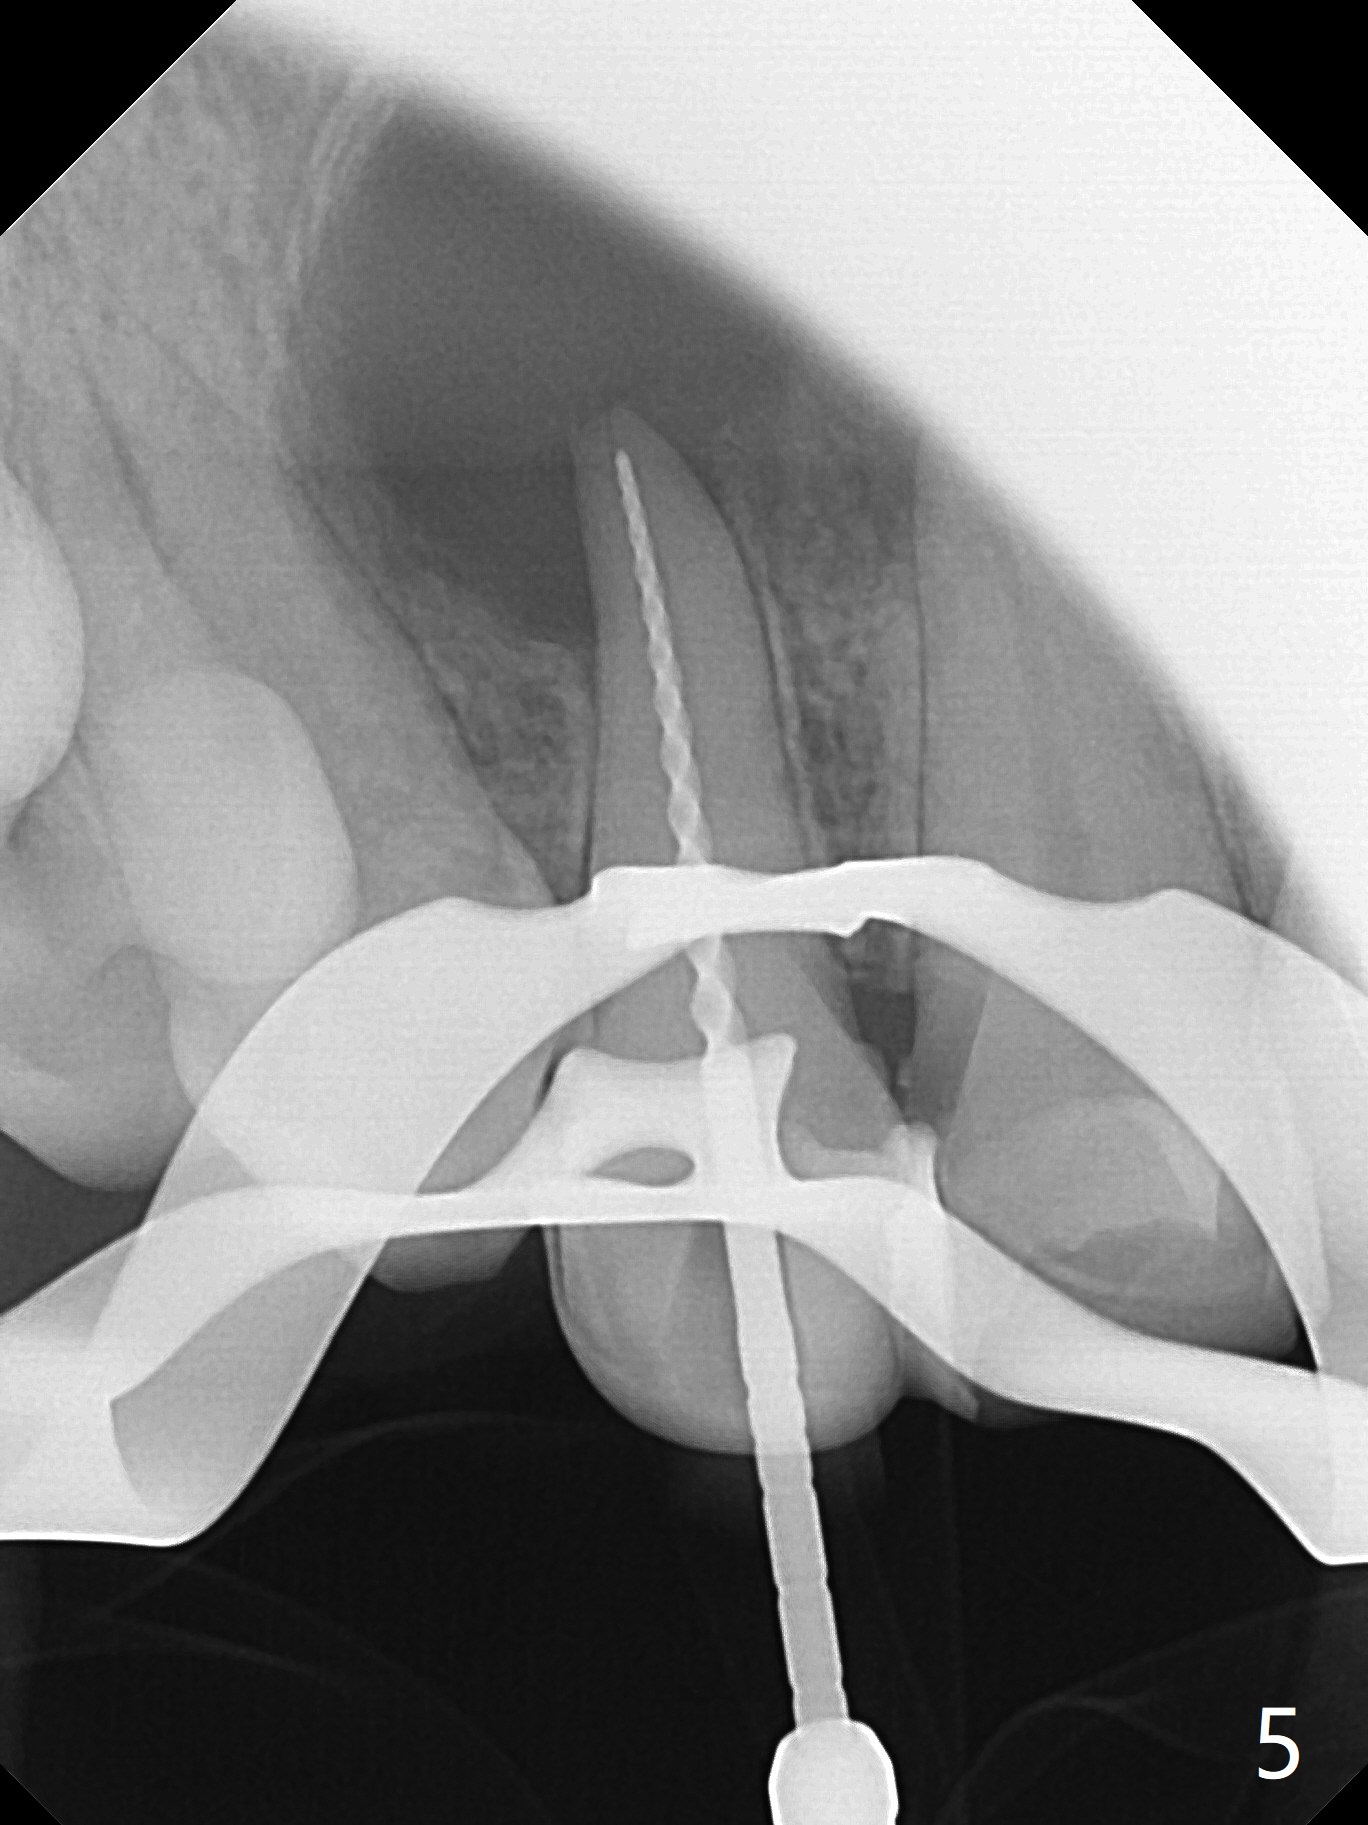

A 47-year-old woman (dental phobic) presented to clinic 9.5 years ago with periapical radiolucency (PARL) at #7 and 9 (Fig.1). RCT was done at #9 because of fistula and symptom 6 months later (Fig.2). While PARL increases at #7 without symptom, that at #9 disappears 8.5 years postop. Three months later, the patient returns for #7 RCT because of the abscesses (Fig.4 *) and pain. Intraop PA is taken with a 30/.06 rotary file in the canal with 19 mm working length (Fig.5). After use of #15 hand file for 20 mm, Ca(OH)2 paste is applied in the canal. When the rubber dam is removed, the abscesses enlarge (Fig.6), which may be related to sodium hypochlorite leakage. A dental explorer is used to try to find a bony opening to the large PARL without success (Fig.7). A postop PA reveals the leakage of Ca(OH)2 paste (Fig.8). Review of the preop PA (Fig.3,9) and intraop PAs (Fig.5,10) shows possible apical resorption and open apical foramen, which is the basis for the paste leakage (Fig.8,11). Careful analysis (with magnification and room light off) of pre- and intra-op PAs should be able to avoid use of #15 hand file out of apical constriction and the complication. The abscess has receded 1 month later (Fig.12). The paste has been resorbed 1 month later (Fig.13). A 30/.06 Gutta Percha is inserted at 18.5 mm (Fig.14 vs. 30/.06 file at 19 mm, 15 file at 20 mm last visit). Fig.15 is the final PA after closure of the access with composite (Fig.15).